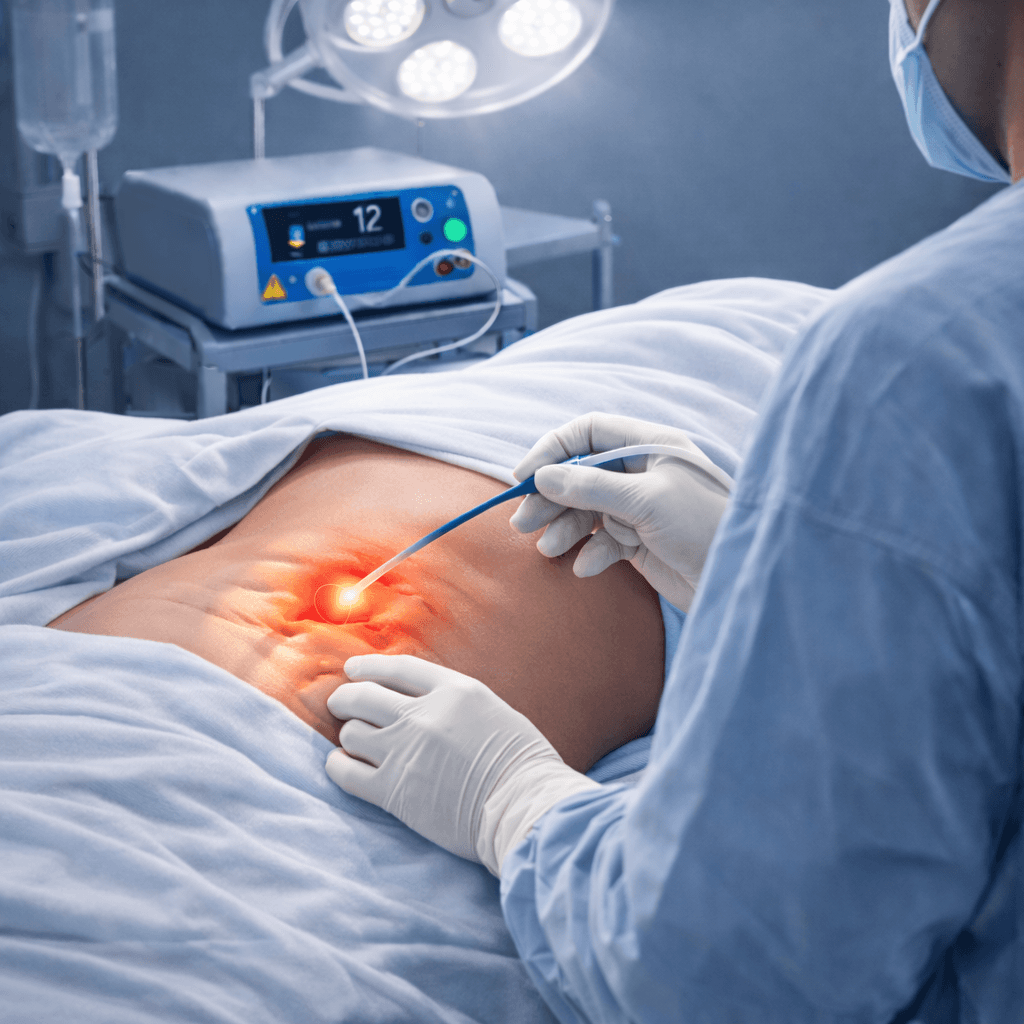

Robust Medical Diode Lasers, Fibres and Staplers

Our Product Applications

Minimally invasive procedures across multiple surgical specialities